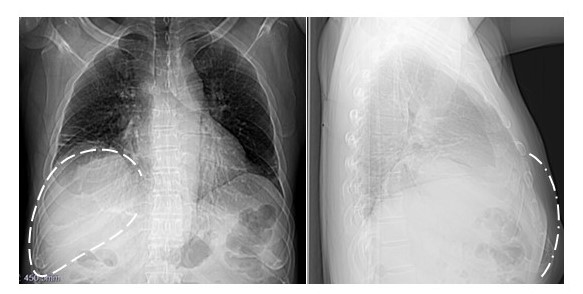

En la radiografía de tórax postero anterior y lateral derecha se aprecia una masa sobre la parrilla costal derecha, que no afecta a los arcos laterales de séptima, octava y novena costillas (Figura 2).